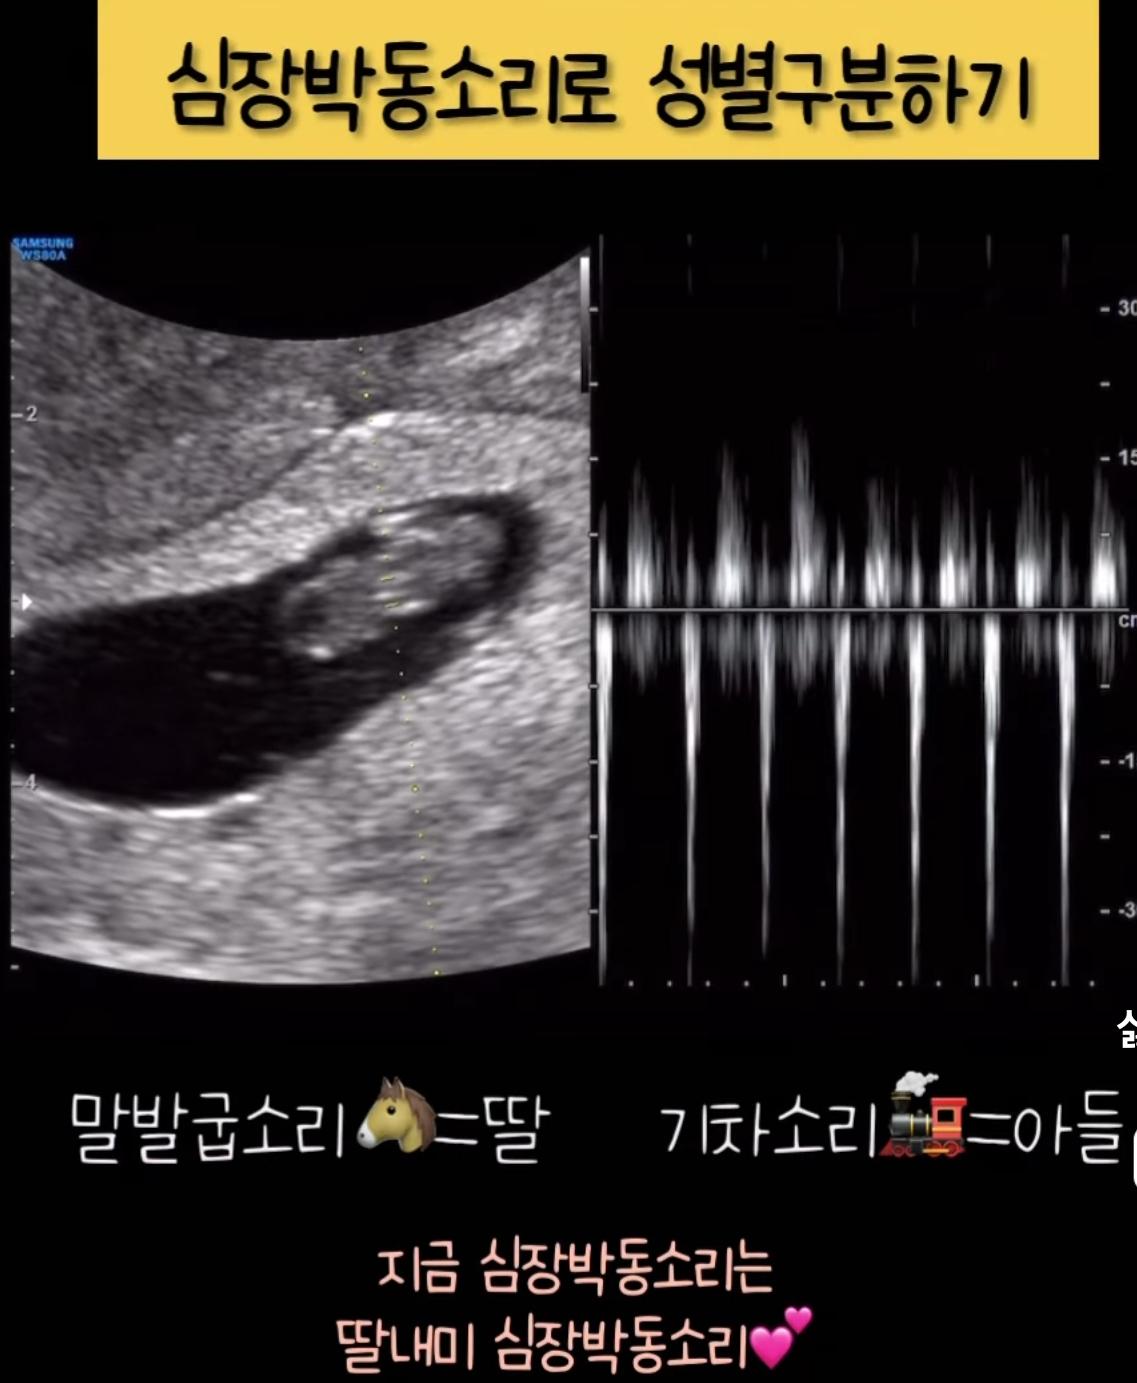

엄마 뱃속 , 남자와 여자 태아의 차이 ㄷㄷㄷ